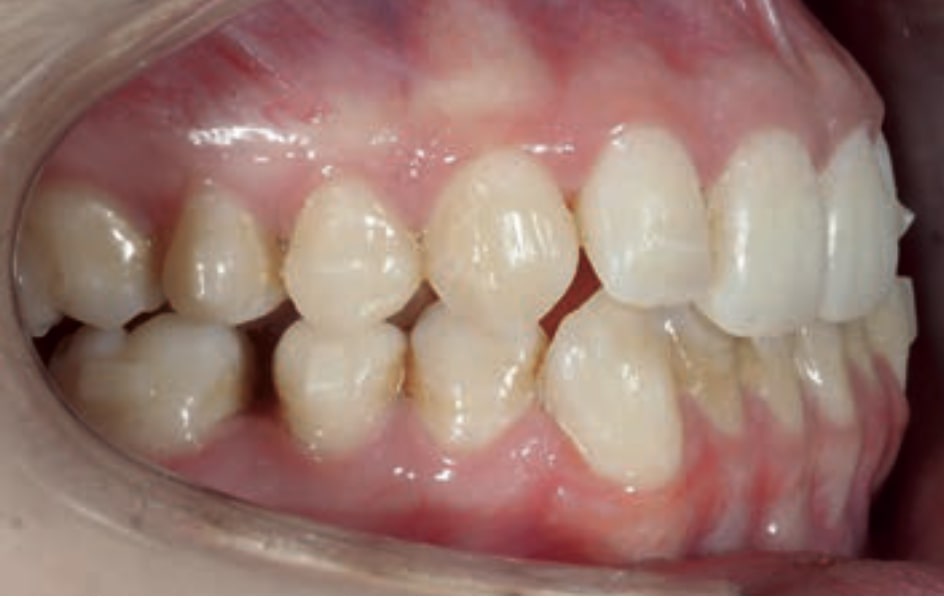

Chief complaint: The patient, a 19-year-old woman, was evaluated to undergo orthodontic treatment using the Angel Aligner Pro system. She presents with a skeletal Class III, mesofacial, with a dental Class III malocclusion and a 2 mm deviation of the lower midline to the left. Teeth 33 and 43 are out of the arch and cortical bone, with a crossbite issue on tooth 33. Fortunately, no functional issues affecting swallowing or breathing have been detected. The patient’s motivation for starting treatment was a general review of her dental and aesthetic health. The soft tissue analysis reveals mandibular protrusion that influences her facial profile. This diagnosis highlights the need for a comprehensive approach to address dental and skeletal misalignments, improving both the patient’s functionality and facial aesthetics.

• Skeletal class III

• Dental Class III, 2 mm deviation of the lower midline to the left. 33 and 43 out of the arch and the cortical bone.

• Crossbite of 33.